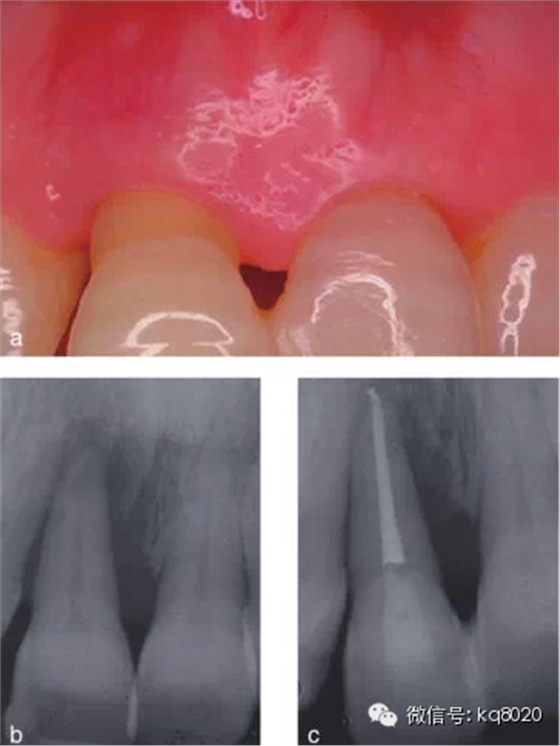

2011年,該研究團隊的隨機對照臨床試驗,選擇已經(jīng)被診斷為臨床無望、伴有牙周牙髓聯(lián)合病變、牙周附著喪失達到或超過根尖的典型病例,分別選擇采用拔牙后固定替代修復(25例)和保存再生治療(25例),進行對照,觀察遠期療效(5年);對于牙髓無活力的聯(lián)合病變患者則先行根管治療,至少觀察3個月后再行牙周手術;再生治療方式包括EMD、GTR、GTR+骨粉、EMD+骨粉、EMD+GTR共5種。結(jié)果顯示,對照組和試驗組均有顯著臨床改善,牙齒功能良好,5年觀察期內(nèi)80%以上患者隨訪無不適;試驗組僅有2顆牙齒療效不佳而予以拔除,平均臨床附著增加7.7±2.8mm,X線顯示骨量增加8.5±3.1mm,PD減少8.8±3mm,均控制在4±1.7mm內(nèi),牙齒松動度均明顯減輕。

結(jié)論證實,牙周治療可改善因骨下袋缺損和重度牙周附著喪失達根尖的無望牙的預后,且這種狀況會保持穩(wěn)定5年以上(圖1、2)。